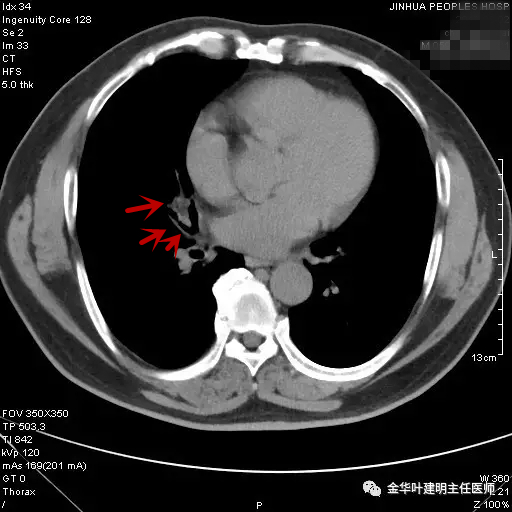

当时嘱其短期复查。后于次年的3月份回院来复查,CT表现如下图:

图四示:次年3月时复查的胸部CT纵隔窗

可见病灶与4个月前的影像表现相仿,并无明显改善,也无显著进展。但呼吸内科及胸外科医生没有局限于现有的诊断,因为其4个月以来,病灶没有任何好转,中叶支气管壁毛糙,仍怀疑不一定仅慢性炎症,需要进一步检查。经过与患者沟通后,决定行纤维支气管镜检查。结果正如医生所担心的,纤支镜提示:右肺中叶可见草莓样新生物,中叶开口粘膜累及 。活检病理:鳞癌。遂经过术前准备,排除手术禁忌证后,转来胸外科由叶建明与谭海栋为其进行了全麻下“胸腔镜下右肺中下叶切除及纵隔淋巴结清扫术”,手术顺利,术后病理示:右中叶中分化鳞癌,累及中叶支气管开口,中间支气管切缘阴性,纵隔淋巴结未见癌转移。